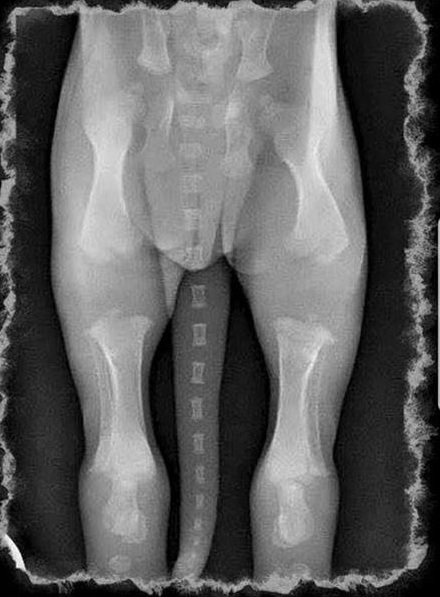

xray pictures